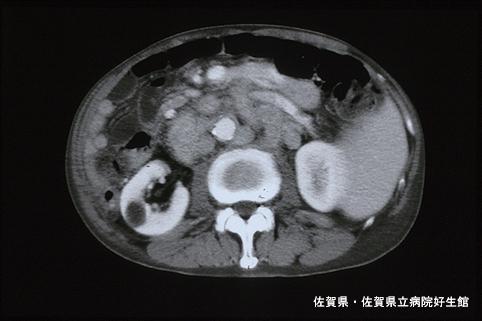

症例提示(所在地,施設名等): 佐賀県・ 佐賀県立病院好生館 (Dr.下田ら)

骨盤部CTでは、S状結腸の壁肥厚と造影による壁の濃染が目立ちます。また、多数の傍大動脈リンパ節の腫大も見られました。

疾患(病理主体)の分類悪性上皮性腫瘍/腺癌

検査方法CT